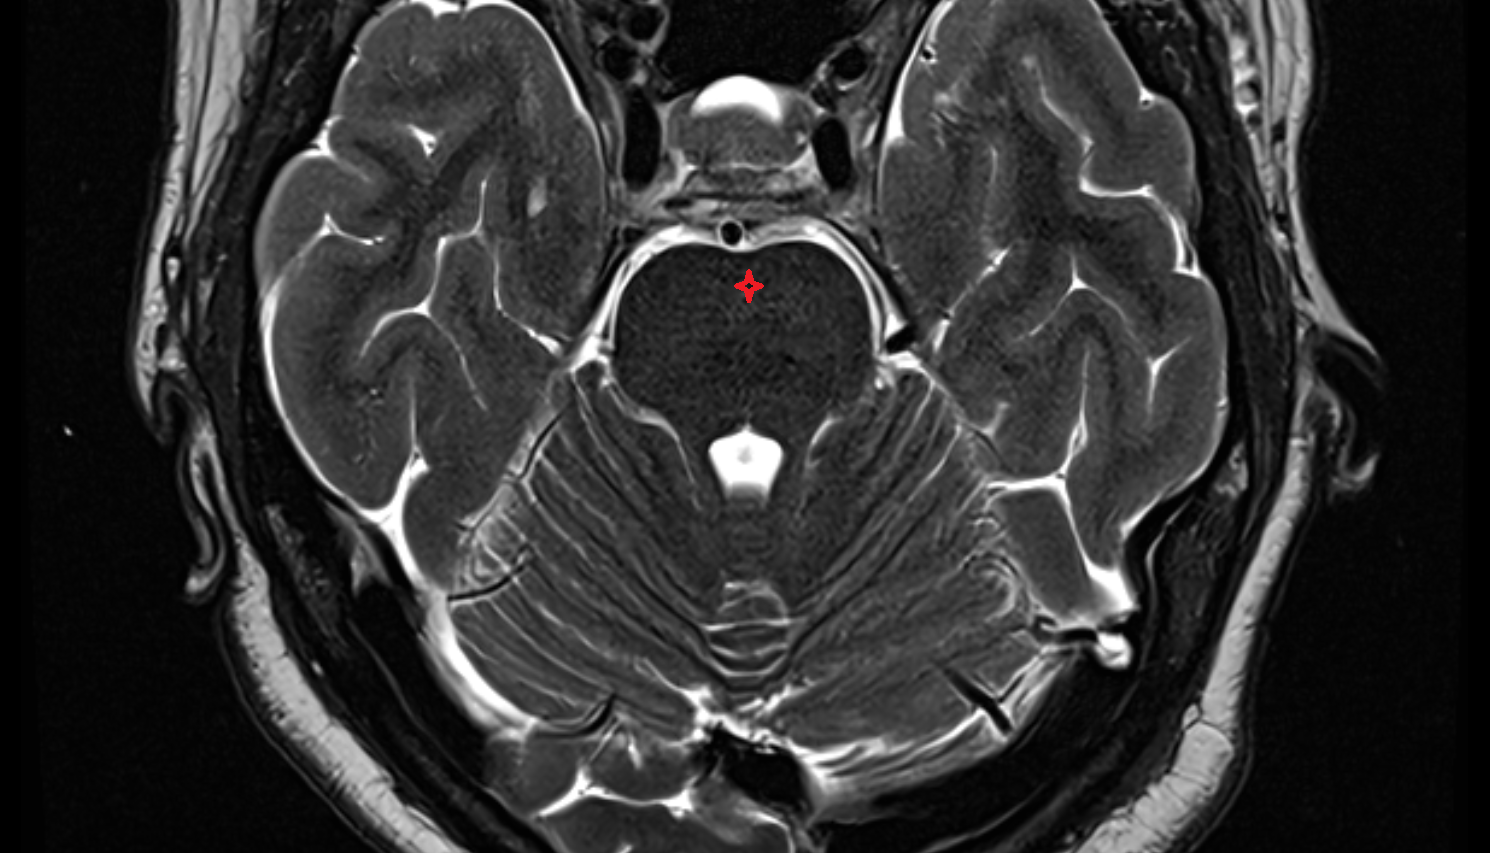

- Cerebellum

- Fourth ventricle

- Cisterna magna